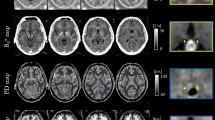

Mass-univariate general linear model (GLM) activation analysis revealed that the habenula had increased activity during the repeating of negative self-cognitions compared to restructuring, in addition to the right PCC, bilateral hippocampus, and the bilateral pOFC (Fig. 2, Supplementary Fig. 1 and Table 2). Of note, neural activation elicited by the repeating of negative self-cognitions was more pronounced in the right hemisphere in both the hippocampus and the pOFC compared to the left hemisphere. As illustrated in Fig. 2d, habenula response increased during both the repeating and restructuring of negative self-cognitions relative to rest. Complete GLM activation results are reported in Supplementary Table 2.

a, b The heatmaps display the general linear model (GLM) results of the cognitive restructuring fMRI paradigm (PFDR < 0.05, KE ≥ 10), with the colour bars representing the t-statistics of the single-sample t test (one-tailed). The warm colour map shows brain regions with increased activity during the restructuring of negative self-cognitions compared to repeating (Challenge > Repeat). The cool colour map highlights structures showing increased activity during the repetition of negative cognitions versus restructuring (Repeat > Challenge). These results confirmed the engagement of the habenula in negative self-cognition processing and were used to inform DCM model node selection. c Consecutive coronal views of the neural activation results of the Repeat > Challenge contrast are presented on the MNI152 template to highlight the habenula cluster showing increased activity during the repeating of negative self-cognitions compared to restructuring. d The line graph plots the group-level blood-oxygen level dependent (BOLD) response (GLM-estimated) of the habenula region-of-interest across the key conditions and when averaged across task epochs (rest, repeat, rest, challenge). The habenula showed sustained activity during the repeating of negative self-cognitions (repeat condition) and evoked response during cognitive restructuring (challenge condition). e Based on the GLM results and past literature on habenula connectivity, the bilateral habenula, right pOFC, PCC, and the hippocampus were selected as model nodes for DCM analysis. f A DCM model centred on the habenula was constructed and estimated for each individual. The model assumed (1) bidirectional endogenous connections between the habenula and the other network regions (grey arrows), in addition to their self-inhibitory connectivity (not shown here); (2) driving input of the experimental stimuli into all network nodes (yellow arrows); and (3) modulatory effects of the restructuring and repetition of negative self-cognitions on the bidirectional connections between the habenula and the PCC, hippocampus, as well as the pOFC (dashed blue arrows). 3-D brain rendering were constructed in BrainNet Viewer with the MNI152 template brain119. DCM dynamic causal model, dlPFC dorsolateral prefrontal cortex, dmPFC dorsomedial prefrontal cortex, HC hippocampus, L left, PCC posterior cingulate cortex, pOFC posterior orbitofrontal cortex, pSMA pre-supplementary motor area, R right, vlPFC ventrolateral prefrontal cortex.